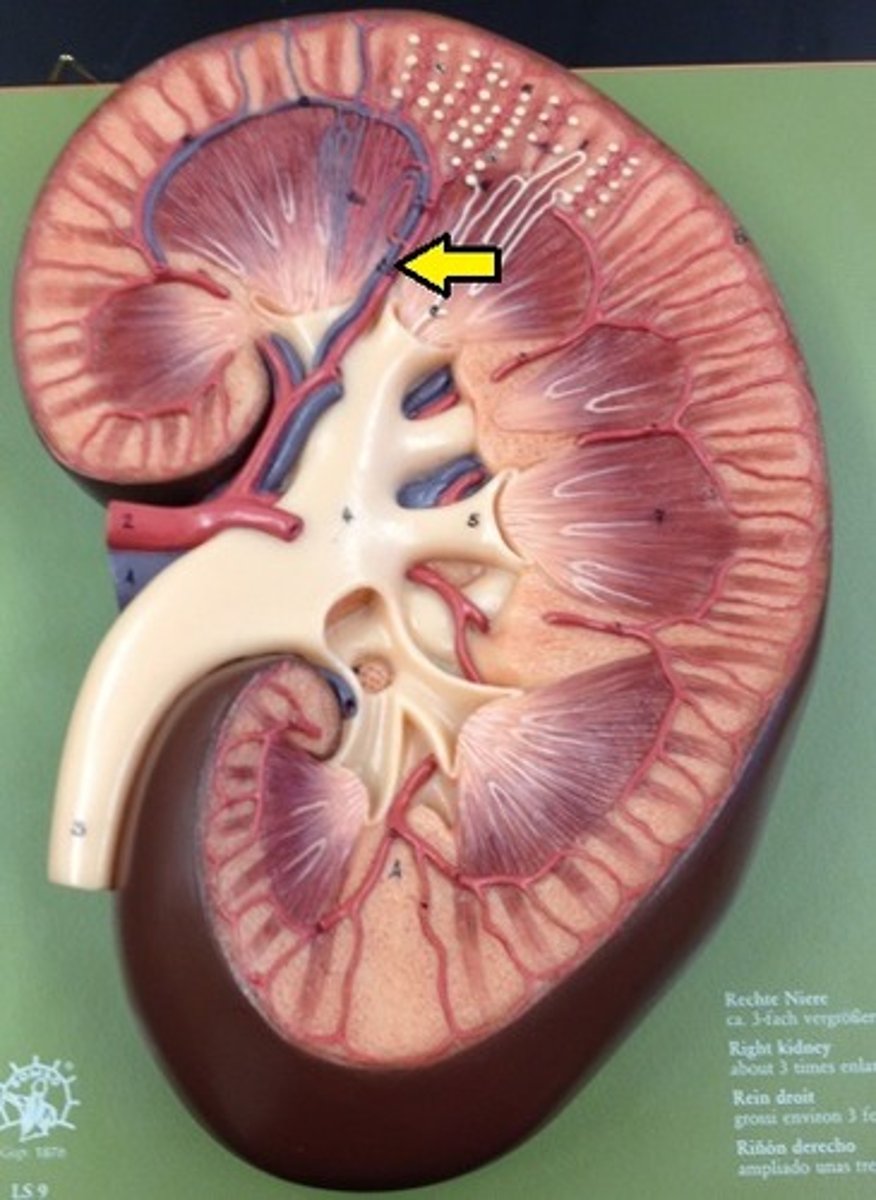

kidney

fibrous capsule

outer covering

renal cortex

renal medulla

renal papilla

major calyx

minor calyx

renal pelvis

renal pyramids

ureter

Pin in the middle

renal columns

renal artery

renal vein

segmental

both vessels

interlobar

both vessels

interlobular

both vessels

arcuate

both vessels